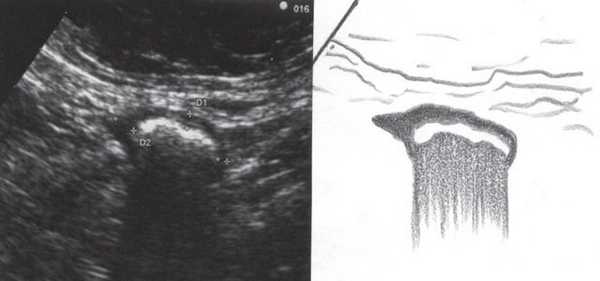

При трансвагинальном УЗИ (рис. 4) также визуализировался фрагмент толстой кишки с утолщенными гипоэхогенными стенками и несколькими округлыми дивертикулами до 1 см в диаметре. Контуры одного из дивертикулов были неровными, он имел звездчатую форму. Отмечались утолщение и повышение эхогенности околокишечной жировой клетчатки по сравнению с контралатеральной стороной. При осмотре в режиме УЗ ангиографии утолщенная стенка кишки и дивертикулы были аваскулярными, окружающая клетчатка - гиперваскулярной.

Рис. 4. Эхографическая картина дивертикулита. Трансвагинальное исследование конвексным датчиком 7,5 МГц.

Во время контрольного УЗИ через 6 мес при осмотре левой подвздошной области толщина стенок нисходящего отдела толстой и сигмовидной кишки не превышала 3-5 мм (рис. 6, а, б), при наблюдении в течение 1 года признаков рецидива не отмечено.

Рис. 6. Эхографическая картина толстой кишки. Контрольное трансабдоминальное исследование конвексным датчиком 3,5 МГц через 6 мес.